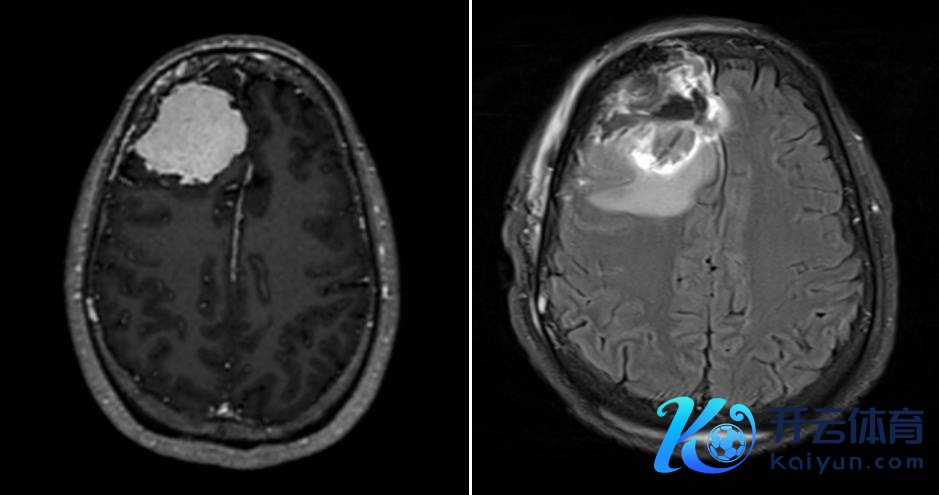

为了寻求精确有用的调节,周大姨盘曲多家病院商榷,最终慕名来到湖南省第二东谈主民病院神经外科三病区。接诊团队为其完善头颅磁共振等防御查验后,明确诊断为右侧额部脑膜瘤。这个大小约5cm×5cm、血供丰富且与硬脑膜紧密粘连的良性肿瘤,不息压迫右侧额叶脑组织,恰是导致周大姨反复头痛的罪魁首恶。

患者术前术后影像府上对比

术前,团队通过高分歧率磁共振、薄层扫描等影像学查验,精确勾画出肿瘤的情状、大小、具体位置,以及与周围神经、血管、脑组织的毗邻关联,完成细腻的手术策动,为术中操作打下坚实基础。